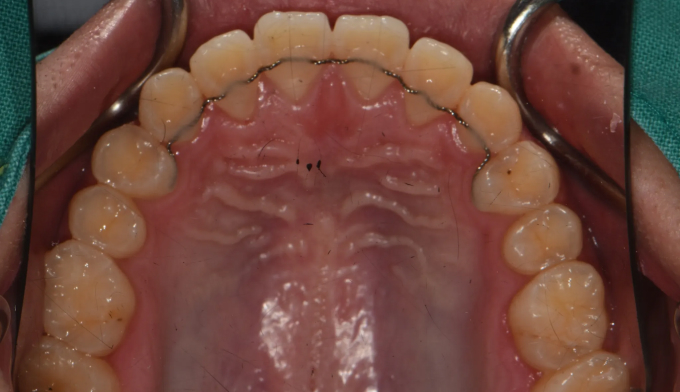

주걱턱 경향을 갖는 청소년들은 개방교합과 덧니를 동시에 갖는 경우가 많습니다. 아래턱의 과도한 성장은 혀의 위치를 아래로 처지게 만들고, 이는 위턱의 폭을 줄어들게 만들어 덧니가 생기기 쉽게 만듭니다. 그리고 과도한 아래턱의 성장은 앞니의 교합을 벌어지게 만들어 개방교합 또한 나타나게 됩니다.

그 정도에 따라 발치가 필요한 경우도 있지만, 성장기의 청소년의 경우에는 최대한 발치 없이 자연스러운 치열과 입매를 만드려고 합니다.

좁아진 위턱 악궁을 확장시켜서 치아를 배열시키고, 과도하게 앞으로 나온 앞니를 미니스크류를 이용하여 후방이동 시킵니다.